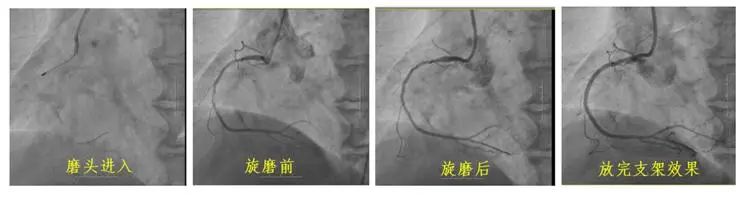

冠狀動脈鈣化因其致密堅硬的病變特征,長期制約著心血管介入治療效果。長春國文醫(yī)院心血管內(nèi)科團隊引入冠狀動脈旋磨技術(shù),在血管內(nèi)超聲(IVUS)實時導航下,以每分鐘15萬轉(zhuǎn)旋磨技術(shù)精準粉碎鈣化斑塊,成功為一名右冠狀動脈100%閉塞的73歲患者實現(xiàn)血管再通。該技術(shù)的成熟應用,標志著醫(yī)院在旋磨技術(shù)處理復雜鈣化病變的臨床可靠性,為更多心血管疾病患者帶來康復希望。

冠狀動脈旋磨術(shù)作為一項先進且高難度的冠脈介入治療技術(shù),在處理冠狀動脈嚴重鈣化病變方面具有獨特優(yōu)勢。其基于精確的“差異切割”原理,通過高速旋轉(zhuǎn)的旋磨頭,精準地對鈣化或纖維化的動脈硬化斑塊進行祛除,同時巧妙避開有彈性的血管組織及正常冠狀動脈,從而極大地降低對血管中膜的損傷風險。該技術(shù)具有精確性高、安全性強、效果持久以及適用范圍廣等顯著特點,能夠有效減輕冠脈狹窄程度,顯著改善心肌供血狀況,為冠心病等心血管疾病的治療開辟新路徑。